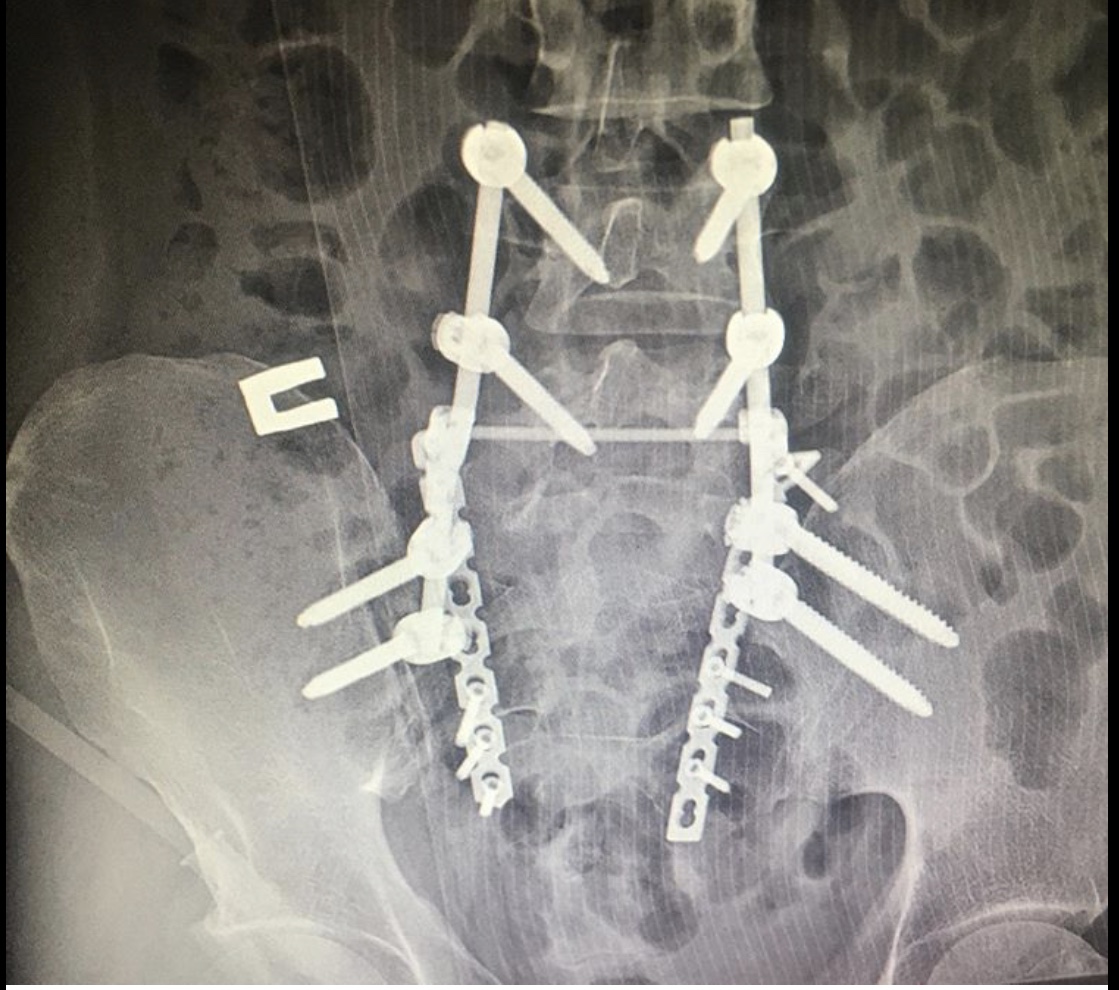

Диагноз неутешительный: двусторонний нестабильный перелом крестца, осложнённый каудопатией и нарушением функции тазовых органов, перелом типа RoyCamille 2 с компрессией корешков конского хвоста.

Как рассказал хирург – травматолог – ортопед нашей клиники Руслан Ильгизарович Закиров, при поступлении пациенту была выполнена стабилизация костей таза в аппарате внешней фиксации. После стабилизации гемодинамических показателей выполнена двусторонняя пояснично-тазовая фиксация, сакротомия на вершине деформации, остеосинтез реконструктивными пластинами.